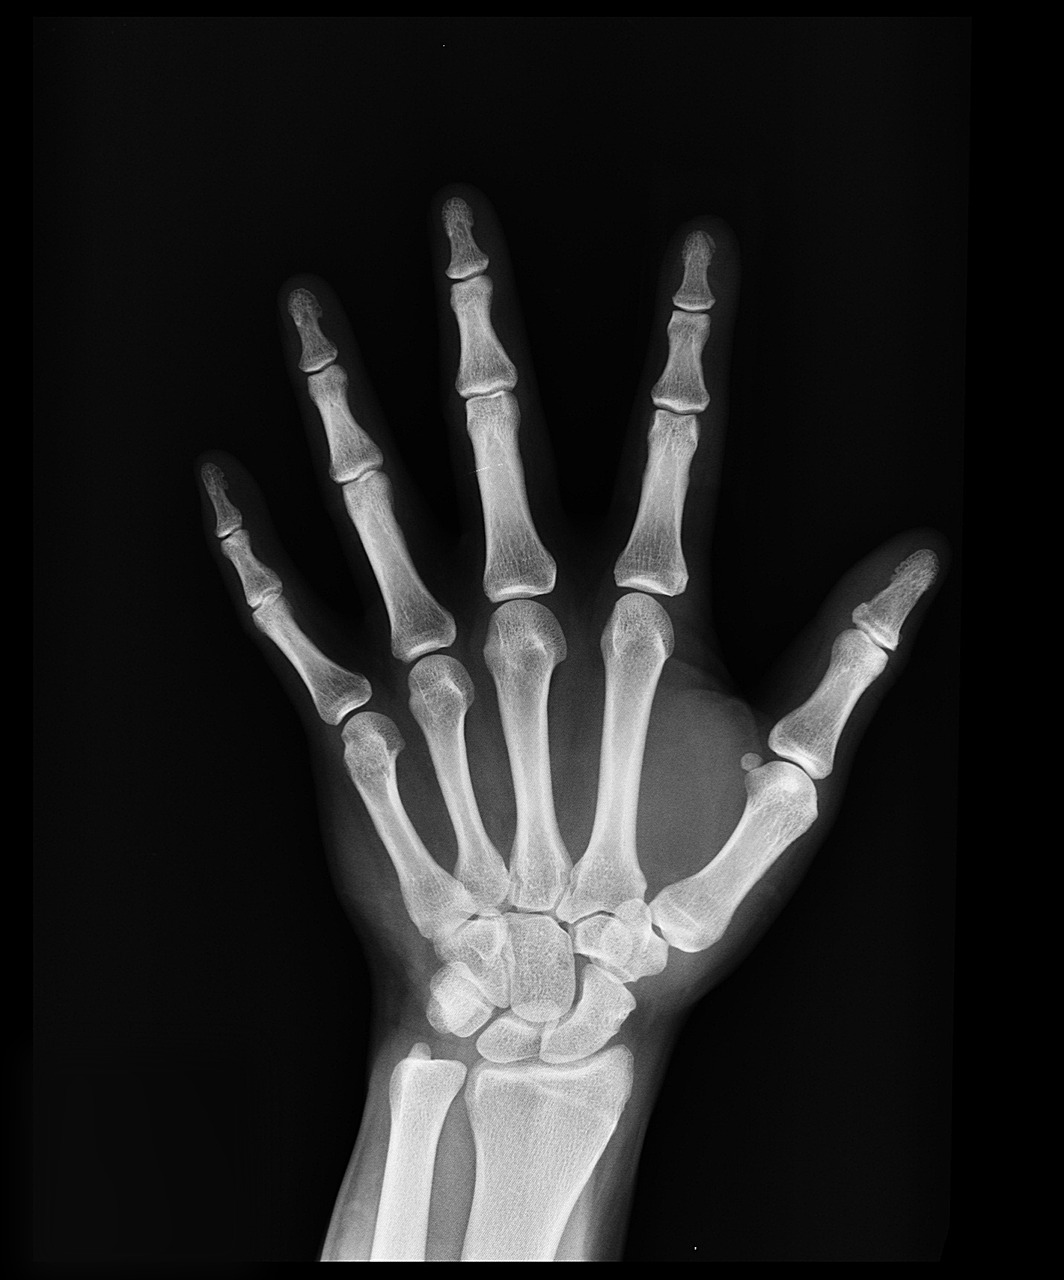

정기적인 건강검진은 뼈 건강을 유지하는 데 중요한 역할을 합니다. DEXA 스캔이라고도 알려진 골밀도 검사는 골다공증 및 기타 뼈 상태를 조기에 발견하여 적시에 개입할 수 있도록 도와줍니다.